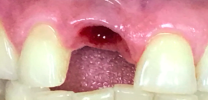

The single tooth implant restoration consists of three parts. Namely, the implant post which replaces the tooth root, the abutment which will support the crown and the prosthetic crown itself. The crown is either cemented onto the abutment or held in place with a screw. The parts of the single tooth implant are bio-compatible to the tissues of the mouth. Therefore, they do not cause any side effects in the oral cavity.